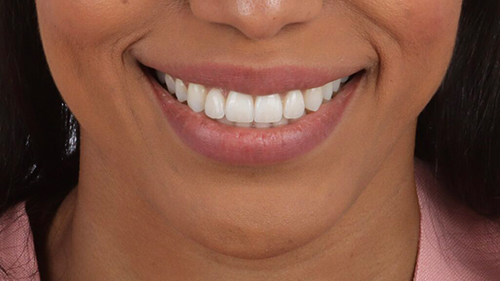

Final situation